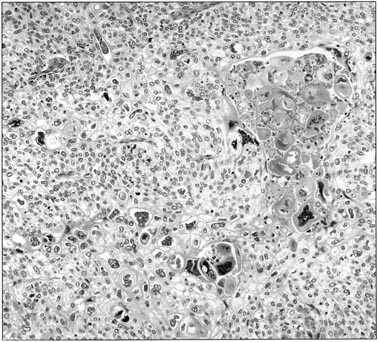

FIGURE 3 | Modern Pathology